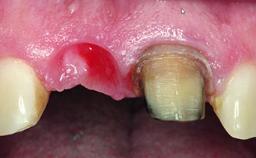

A healthy 28-year-old female patient presented for a consultation on treatment options to restore her upper right central incisor. At the clinical examination, the tooth responded to percussion and palpation. The gingiva was red and slightly swollen, with a mid-facial probing depth of 10 mm. The upper right lateral incisor showed no signs or symptoms, did not respond to exploration and percussion, and the vitality test was positive. The periapical radiograph revealed that tooth 11 had been endodontically treated, with no lesion evident at the apex. A small radiopaque calcified structure surrounded by a narrow radiolucent zone (3 × 3 mm) was present at the apex of tooth 12.